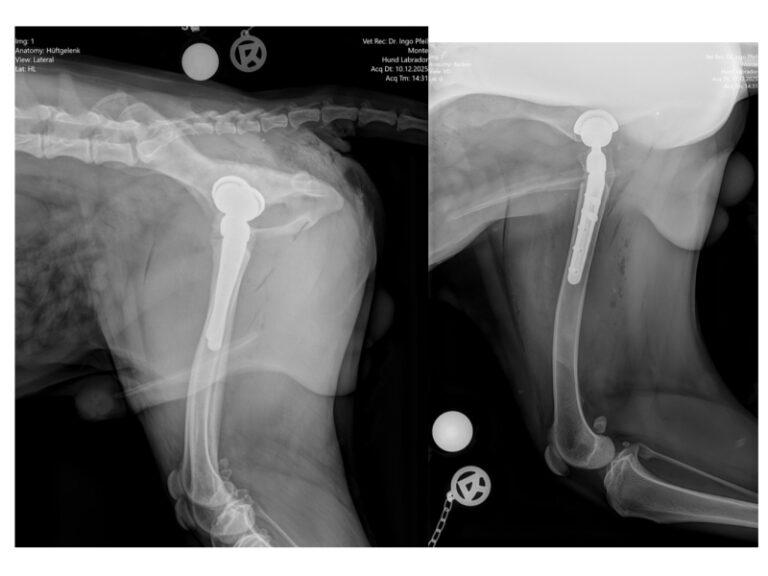

Unser Jungspund hat in diesem Jahr das teuerste Weihnachtsgeschenk bekommen, nämlich sein zweites künstliches Hüftgelenk. Nachdem Dr. Pfeil die Kontrollröntgenbilder für so gut eingeschätzt hat, dass nunmehr bereits die andere stark deformierte Hüfte ersetzt werden kann, folgte eine Woche später schon die Operation in Dresden.

Alles verlief wieder komplikationslos und munter kam das Hündchen wieder nach Hause. Nun steht uns allerdings wieder eine schwere Zeit bevor, heißt es doch, drei Monate lang strenge Boxenruhe und nur 3 x 5 Minuten am Tag Gassigehen. Leider versteht unser junger Patient nicht so recht was das soll und benimmt sich dementsprechend. Es kostet nicht nur Kraft, sondern auch so einige Nerven ihn täglich zu betreuen. Aber jeder Tag ist ein geschaffter Tag und dem Ziel wieder ein Stückchen näher. Und das Ziel ist nun einmal, dass Monte endlich schmerzfrei und glücklich über die Wiesen rennen kann.

Leider stellte Dr. Pfeil in der Tierklinik fest, dass sich die Hüften innerhalb der letzten vier Wochen derart verschlechtert hatten, dass eine DARthroplastik nicht angewandt werden konnte und nunmehr beide Hüften durch künstliche Gelenke ersetzt werden müssen. Als erste OP wurde nun das linke Hüftgelenk ersetzt. Alles ist gut gelaufen und das Entscheidende ist nun der Heilungsprozess, was bei so einem Wirbelwind eine große Herausforderung darstellt.

Zur Unterstützung erhält der junge Patient nun für ein paar Wochen ein Beruhigungsmittel. Es ist schon erstaunlich, wie gut Monte die Box und die Ruhephasen annimmt, allerdings ist er kaum zu halten, wenn er dann seinen fünf Minuten „Spaziergang“ unternehmen darf. Trotzdem geht er danach ganz brav wieder in die Box zurück und bekommt zur Belohnung ein Leckerchen.